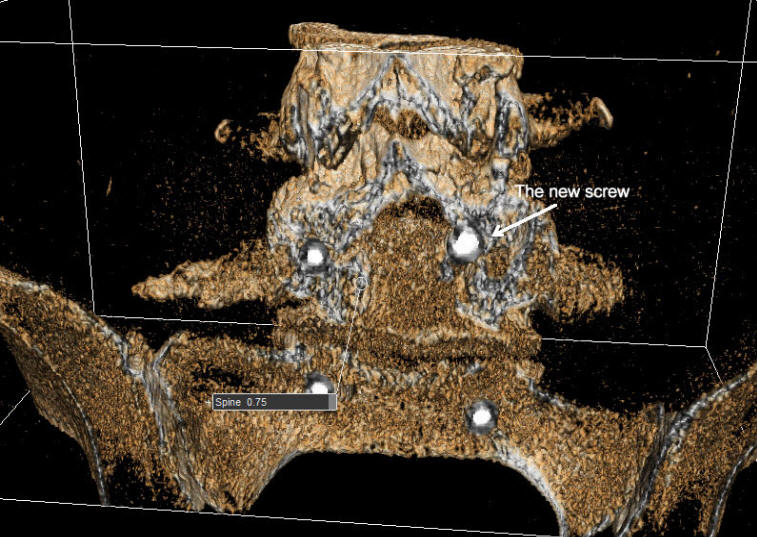

The patient was sent for new MRI of the lumbar spine with dynamic studies and CT-scan of the operated area and lab investigations. The CT-scan with reconstruction using ORS Visual showed the right upper screw touching the root. It was decided to explore the the site of surgery and resolve all her problems.

The old incision refreshed and the four screws exposed. The right rod was removed. Using Inomed ISIS transpedicular screw protocol, the right lower screw and both left screws did not gave EMG response even with 15 mA DNS stimulation. The right upper screw gave response even with 8 mA DNS stimulation. The construct is of Expedium brand. The type of the screw is polyaxial. It was removed and inspection of the screw cavity with feeler confirmed that it is located in the soft tissues. As seen in the figure below, the screw was inserted vertical to the sagittal plan and it was media at the level of the pedicle and outside the body of the L5. Foraminotomy right L5  and S1 roots. They were responding even with 1-2 mA DNS stimulation. Using Stryker XIA 3 system a new polyaxial screw 6.5x50 mm was inserted from near upper point and directed medially. All the screws now not responding even with 15 mA DNS stimulation. MAC cross connector 42 mm was applied to gain more stability of the construct. The harvested bone melt and applied lateral to the rods. Routine closure of the wound.

The patient is a difficult case to estimate. Only with use of special software such as ORS Visual explained the real wrong position of the screw.

The upper screw looking as be inside the canal, but this picture after removing the fractured fragments and the root was inspected visually and even the screw is thicker than the others, but it is actually inside the pedicle and the 15 mA DNS stimulation of the screw did not trigger any response.